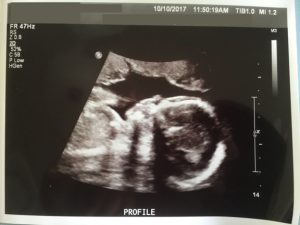

高層次超音波照 – 側面臉部輪廓

我們在的過程中,經由Mrs. A的高層次攝影中看見強健的小寶寶,她一直誇獎寶寶好可愛,真是健康,我相信她在這個職業7年以上經驗的她,應該看過許多不一樣的寶寶,所以也不能不信。每個爸媽都希望小寶寶在媽媽的肚子裡健康成長,不希望有身體的缺陷或是遺傳疾病。最後Mrs. A 列印出臉部特寫及側面臉部輪廓超音波照讓我們帶回家。